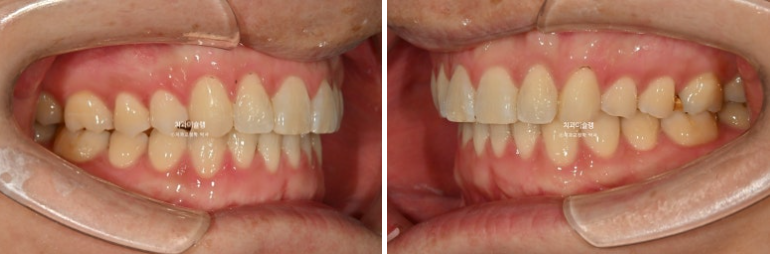

25.04~25.10

25.04

중심선이 맞지 않고 잇몸라인이 들쑥날쑥 합니다.

잇몸라인이 들쑥날쑥한 이유는 덧니 때문입니다.

어금니 교합관계는 좌우가 다른 상태라 위아래 중심선이 맞지 않습니다.

이렇게 측절치만 튀어나가있고 중절치는 옥니처럼 안으로 들어간 상태를 2급 2류 부정교합이라고 합니다.

25.08

치료시작 4개월차 모습입니다.

윗니배열은 완벽하며

아랫니 배열이 조금 부족합니다.

약 2개월간 교정을 더 진행하여 10월, 드디어 장치를 뗍니다.

이제 전후 비교 보겠습니다.

총 치료기간은 6개월 입니다.

중심선 불일치는 부분교정의 한계점으로 그대로 덧니를 포함한 배열만은 완벽합니다.

특히 아래 앞니 중 튀어나와있던 파란 화살표 앞니는 배열 과정에서 잇몸라인도 자연스럽게 주변과 맞아집니다.